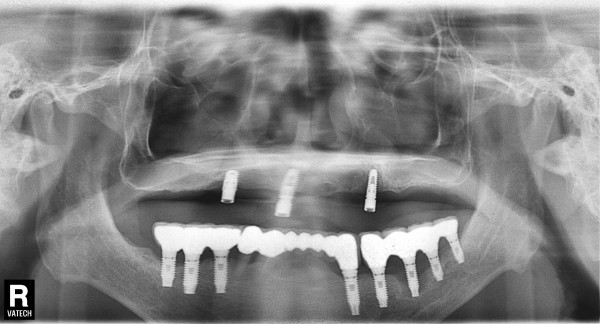

75세 남자 좌ㆍ우측 상악 상악동거상술및임플린트식립